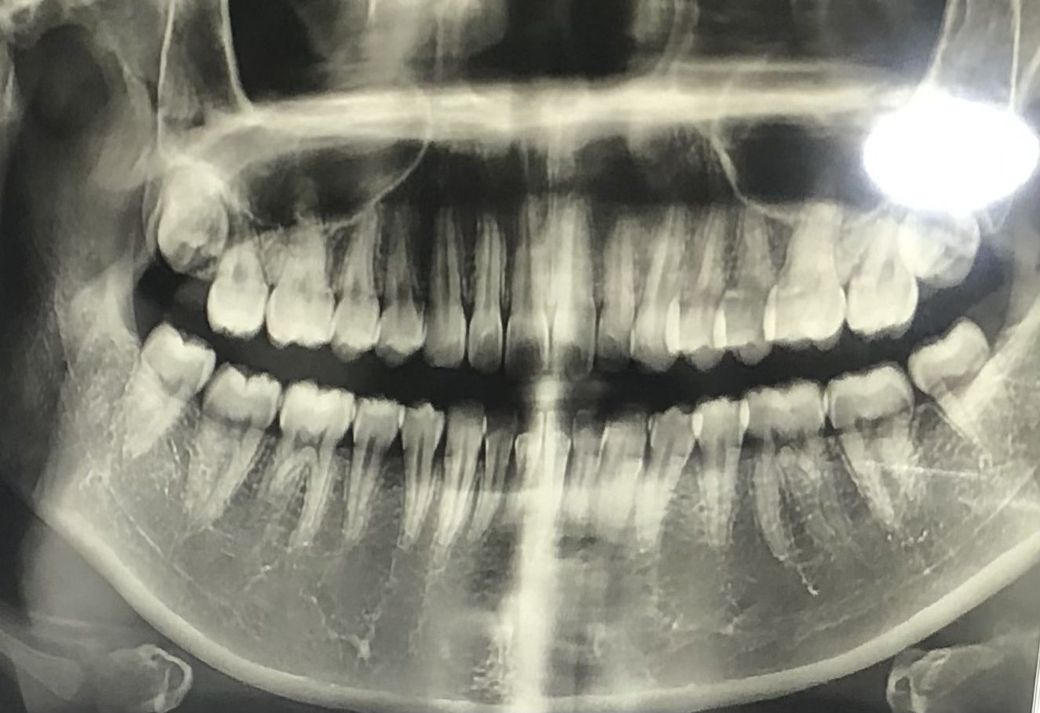

사진은 작년 11월 찍은거여서 지금은 세 개는 나왔고 오른쪽 윗 사랑니는 나오고 있는 중이에요.

현재 사진으로 보아서는 신경과의 근접 정도는 크지 않아 보입니다. 또한 위쪽 사랑니는 정상적인 맹출이 아니므로 발치하는 것을 권해드리며 현재 아래 2개의 사랑니 역시 맹출 방향은 괜찮으나 사랑니까지 구강 관리를 하기에 상당히 어려움이 있습니다. 따라서 젊었을 때 사랑니를 뽑는 것을 권해드리고 현재로서는 후유증이 나타날 정도로 신경과 근접하지 않습니다.

사랑니아래 2개는 신경관과 거리가 어느정도 있기때문에, 발치하면서 신경손상이 있거나 감각이상이 생길 가능성은 별로 없어보입니다.

양쪽 아랫 사랑니 뿌리가 신경관과 근접해 있습니다. 이런 경우 발치후 감각이상 나타나기도 하지만

그 가능성은 희박하니 우선 사랑니 뽑는 것을 권합니다. 그냥 두면 바로 앞 어금니에 손상을 줄 수 있으니

지금 뽑는 것이 좋을 듯 합니다.